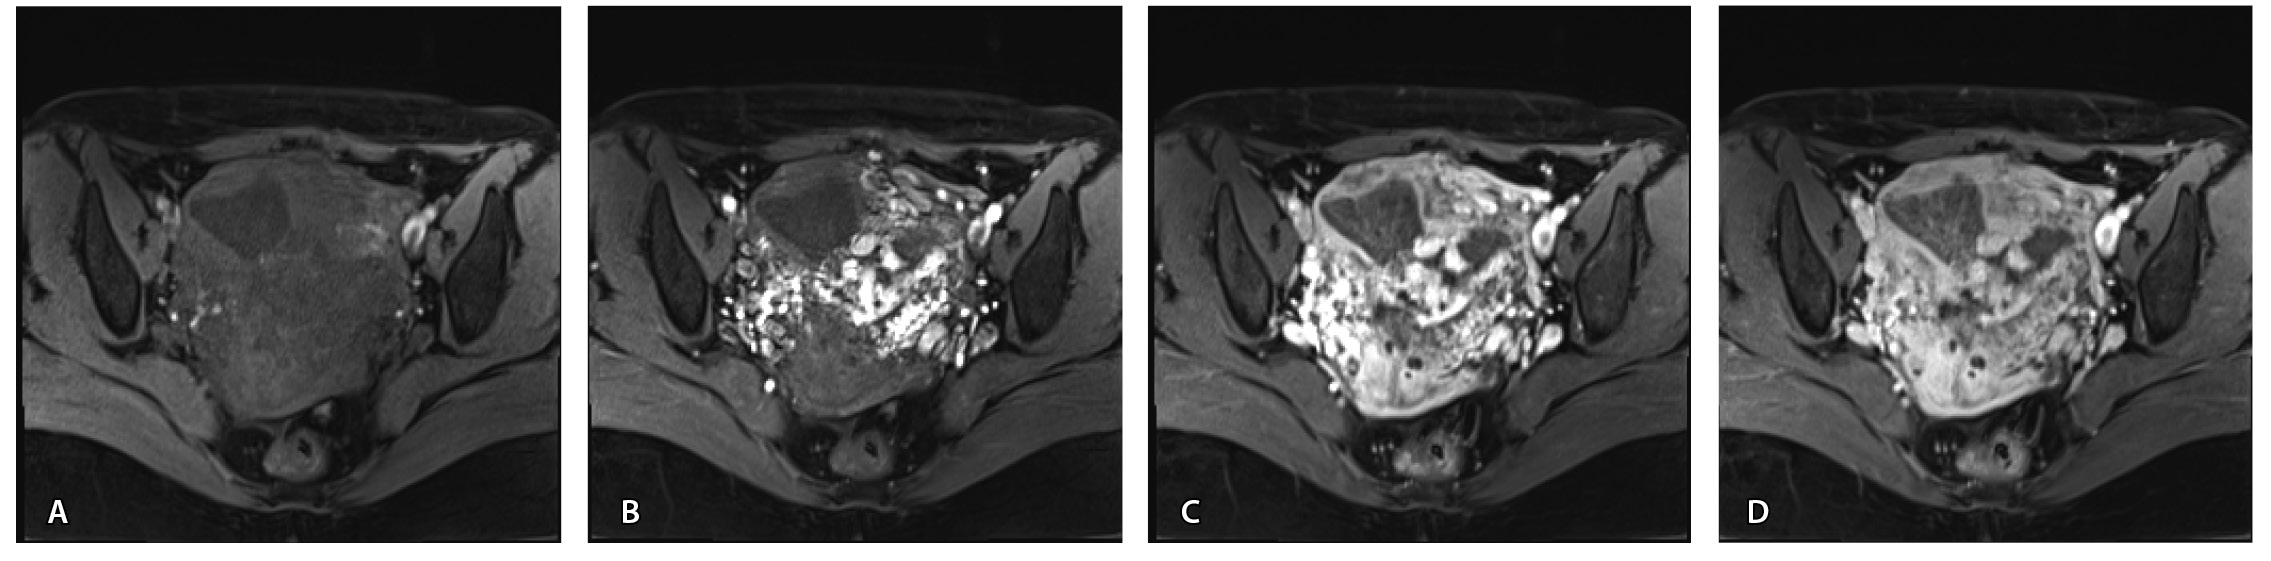

Пациентке выполнено МРТ-исследование на МР-томографе Siemens MAGNETOM Verio с индукцией магнитного поля 3T, с использованием стандартных катушек, в режимах Т1-взвешенного изображения (ВИ), Т2-ВИ, Т2-FS, FIESTA, DWI с получением изображений в сагиттальной, корональной и аксиальной плоскостях, динамическое внутривенное контрастирование (гадопентетовая кислота 0,2 мл/кг массы тела). Матка увеличена в размерах, с признаками снижения зональной дифференциации стенок, усиленным сосудистым компонентом, полость матки расширена с наличием примеси геморрагического содержимого, неравномерным утолщением эндометрия и пристеночными компонентами слизистой. В нижнем маточном сегменте определяется несостоятельный рубец от кесарева сечения, с наличием участка резко истонченной пролабирующей стенки матки слева и наличием дополнительного образования неоднородного сигнала, суммарно до 4,0 × 2,3 × 3,2 см, представленного фрагментами мягкотканного хориона (изоинтенсивного на Т2-ВИ), достигающего серозного покрова матки, и патологического сосудистого компонента в виде расширенных полнокровных сосудов, зон неоангиогенеза (рис. 1). На DWI признаков ограничения диффузии не определялось.

Рис. 1. Остатки вросшего хориона в несостоятельный рубец от кесарева сечения. Магнитно-резонансная томограмма, Т2-взвешенное изображение в сагиттальной (А), корональной (Б), аксиальной (В) плоскостях. Признаки наличия в проекции несостоятельного рубца от кесарева сечения фрагментов ткани вросшего хориона изоинтенсивного сигнала (отмечен звездочкой), с распространением до серозного покрова матки. Стрелками указаны гипоинтенсивные сосуды, зоны неоангиогенеза, артериовенозные сосудистые коллатерали

По наружной поверхности нижнего маточного сегмента и в параметрии определяется наличие полнокровной сосудистой сети с артериовенозными анастомозами. При контрастировании визуализируются фрагментарные участки гиперваскулярного накопления контраста вышеописанным образованием в рубцовой нише, а также определяется наличие артериовенозной сосудистой мальформации (рис. 2).

Рис. 2. Магнитно-резонансная томограмма, динамическое контрастное усиление в режиме Т1-взвешенного изображения FS. До контраста (А), в раннюю артериальную фазу (Б), паренхиматозную фазу (В), выделительную фазу (Г) определяются многочисленные патологические сосуды, зоны неоангиогенеза, сосудистые шунты как в стенке матки, так и в параметрии по типу артериовенозной мальформации